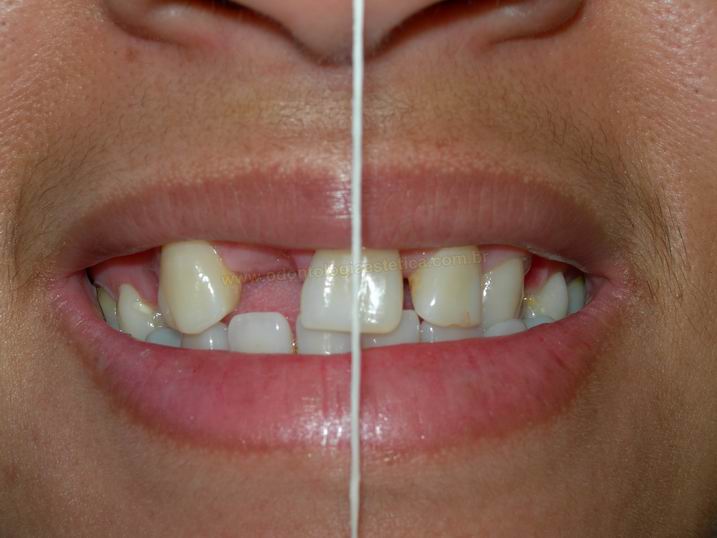

VISTA FRONTAL (anterior ao tratamento) |

VISTA FRONTAL (posterior ao tratamento) |